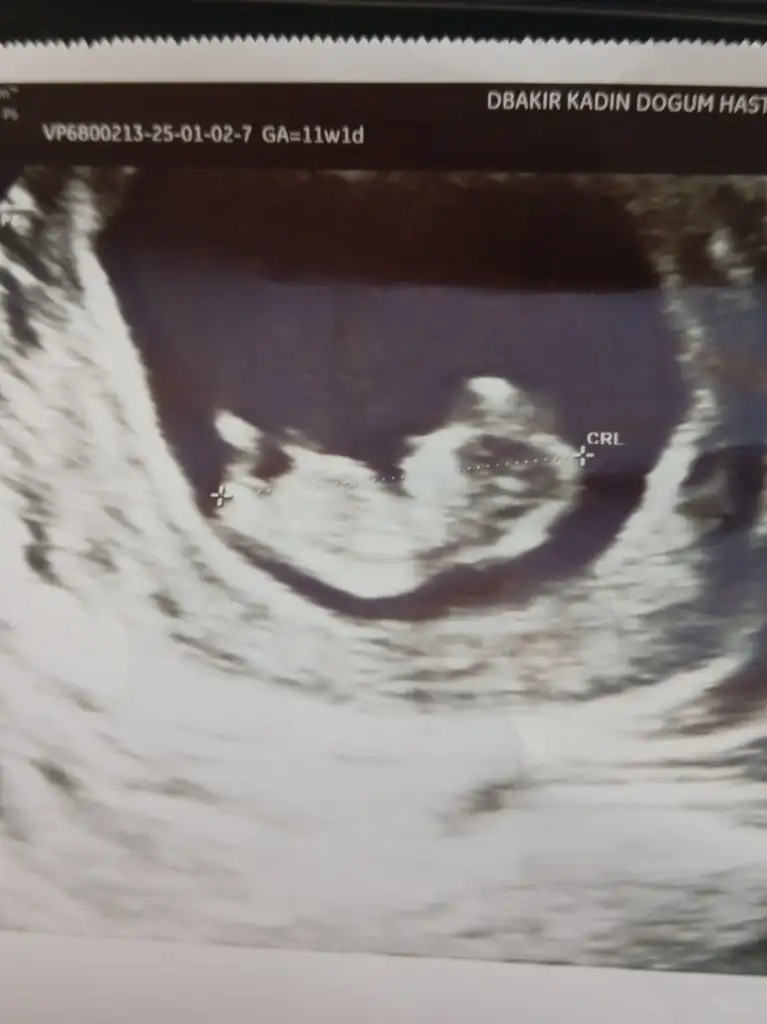

Kese uzunsa erkek yuvarlaksa kız mi ?

Kızlar bı arkadaş keseye göre tahmin yapıyor ve hep tutuyormuş iki oğlunu da bu şekilde cok yeniyken bile tahmin etmiş...ogullarinda kesesi hep uzunmuş muz gibi...yuvarlak ve yuvarlağa yakın olanlar hep kızdır diyor..ve bayağı emin konusuyor..benimki şişman bı fasulye gibi oo kesin kız görürsün dedi...sizlerin keselerinin şekli nasıldı ve cinsiyet neydi konusalimmi 😊